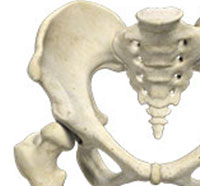

The hip plays an important role in supporting the upper body weight while standing, walking and running, and hip stability is crucial for these functions. The femur (thigh bone) and acetabulum (hip bone) join to form the hip joint, while the labrum (tissue rim that seals the hip joint) and the ligaments lining the hip capsule maintain the stability of the hip.

The hip joint is a "ball and socket" joint. The "ball" is the head of the femur or thigh bone, and the "socket" is the cup-shaped acetabulum. The joint surface is covered by a smooth articular surface that allows pain-free movement in the joint.

The hip is a ball and socket joint comprising of the femur (thigh bone) and the pelvic bone. The head of the femur (ball) articulates with a cavity (socket) called the acetabulum in the pelvic bone. To facilitate smooth and frictionless movement of the hip joint, the articulating surfaces of the femur head and acetabulum are covered by spongy articular cartilage.